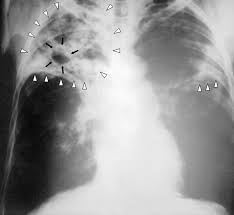

Светски дан туберкулозе

Обележава се